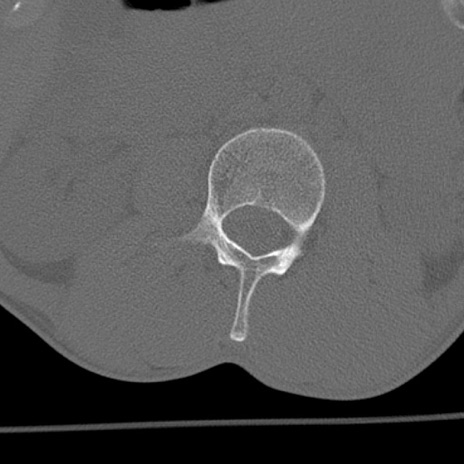

症例3 腰椎CT(横断像)

腰椎CT